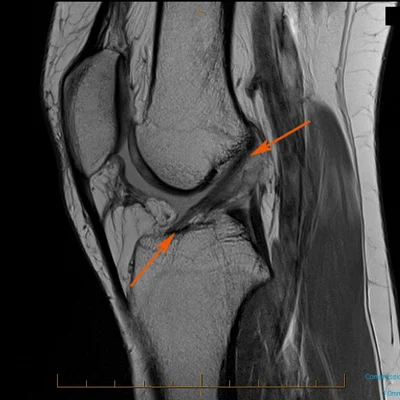

Pre Operative Knee

“The research tells us that a course of preoperative knee rehab helps in the case of meniscus, ACL, and total knee surgeries.”